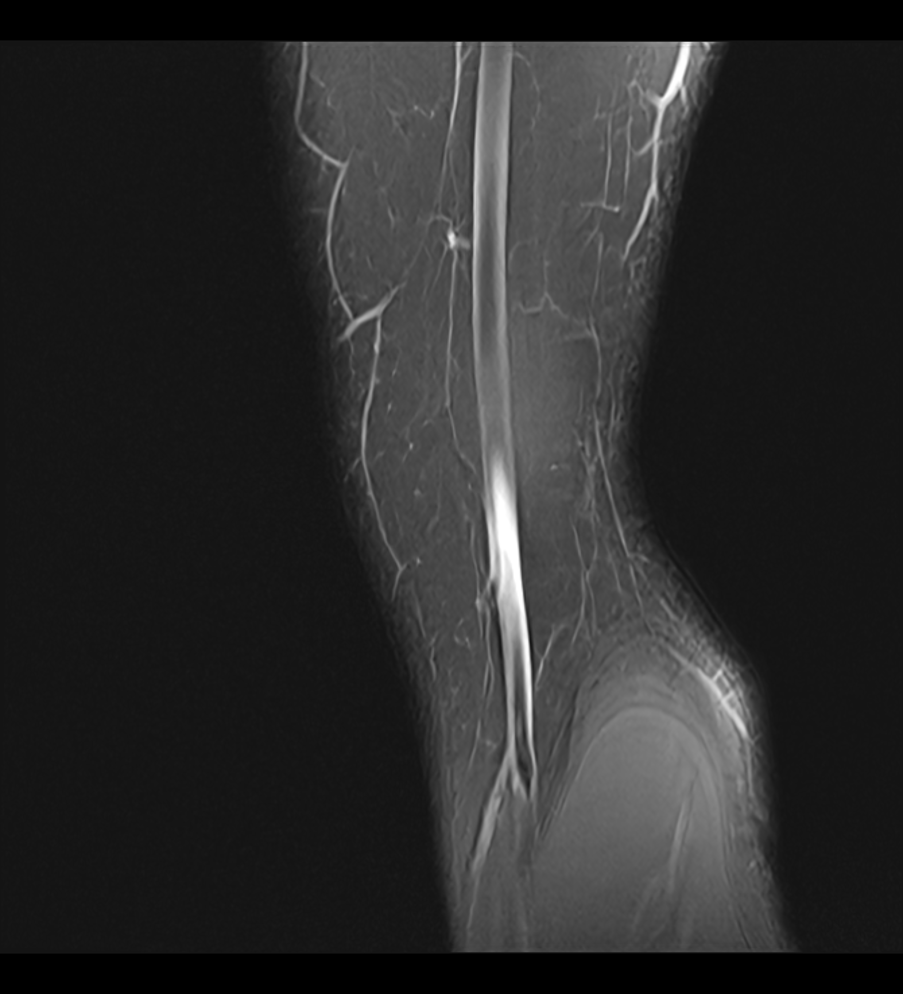

Ici, quelques lésions, elles-mêmes fragiles, qui parcourent je ne sais quel organe de mon corps. Si on veut bien y croire, on pourrait voir dans ces vaisseaux abîmés par le temps, une beauté rageuse, un questionnement ouvert sur toutes les temporalités et la vie.  Comme tous ceux qui l’ignorent encore j’ai mal, mal de cette fragilité humaine quantique, diffuse et qui toujours s’échappe de ma volonté.